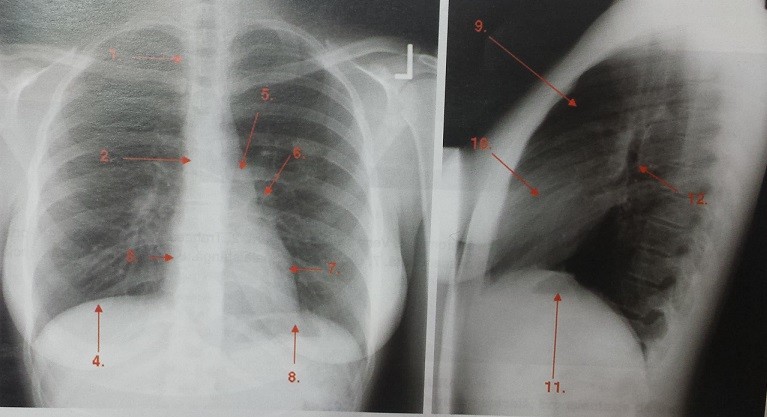

Generalitati radiografia pulmonara toracica este cea mai frecventa examinare radiologica. Ct computer tomograf. Seara acum 3 saptamani am facut o radiografie la coloana lombara dar as dori sa fac o examinare la intreaga coloana. In zona lombara nu am decat o discreta zi probabil e in partea superioara a coloanei.

Radioanatomia Aparatului Respirator Proceduri Medicale